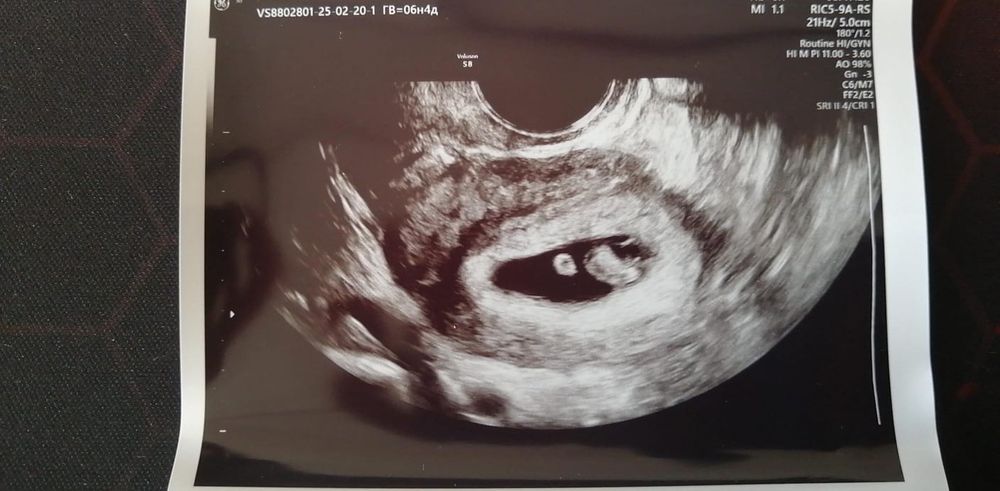

Первое узи 6н4д.

София, Ну мне сначала даже сказали что по ктр 6.6, но написали 6.5. В принципе несколько дней никуда не влияют, я просто рада что в матке и растет)

Анна, Спасибо) Я вообще в 7 недель идти хотела, чтобы с гарантией, настраивала себя сидела что ничего страшного если еще не будет сейчас сердцебиения, просто 7 недель на воскресенье выпадает, праздник они не работают. Но хорошо, малыш показался, сердечко услышали)

Ура, красивая бусинка 😍 Наверное эмоции непередаваемые)))

Какая красивая бусинка, растите✨🤞